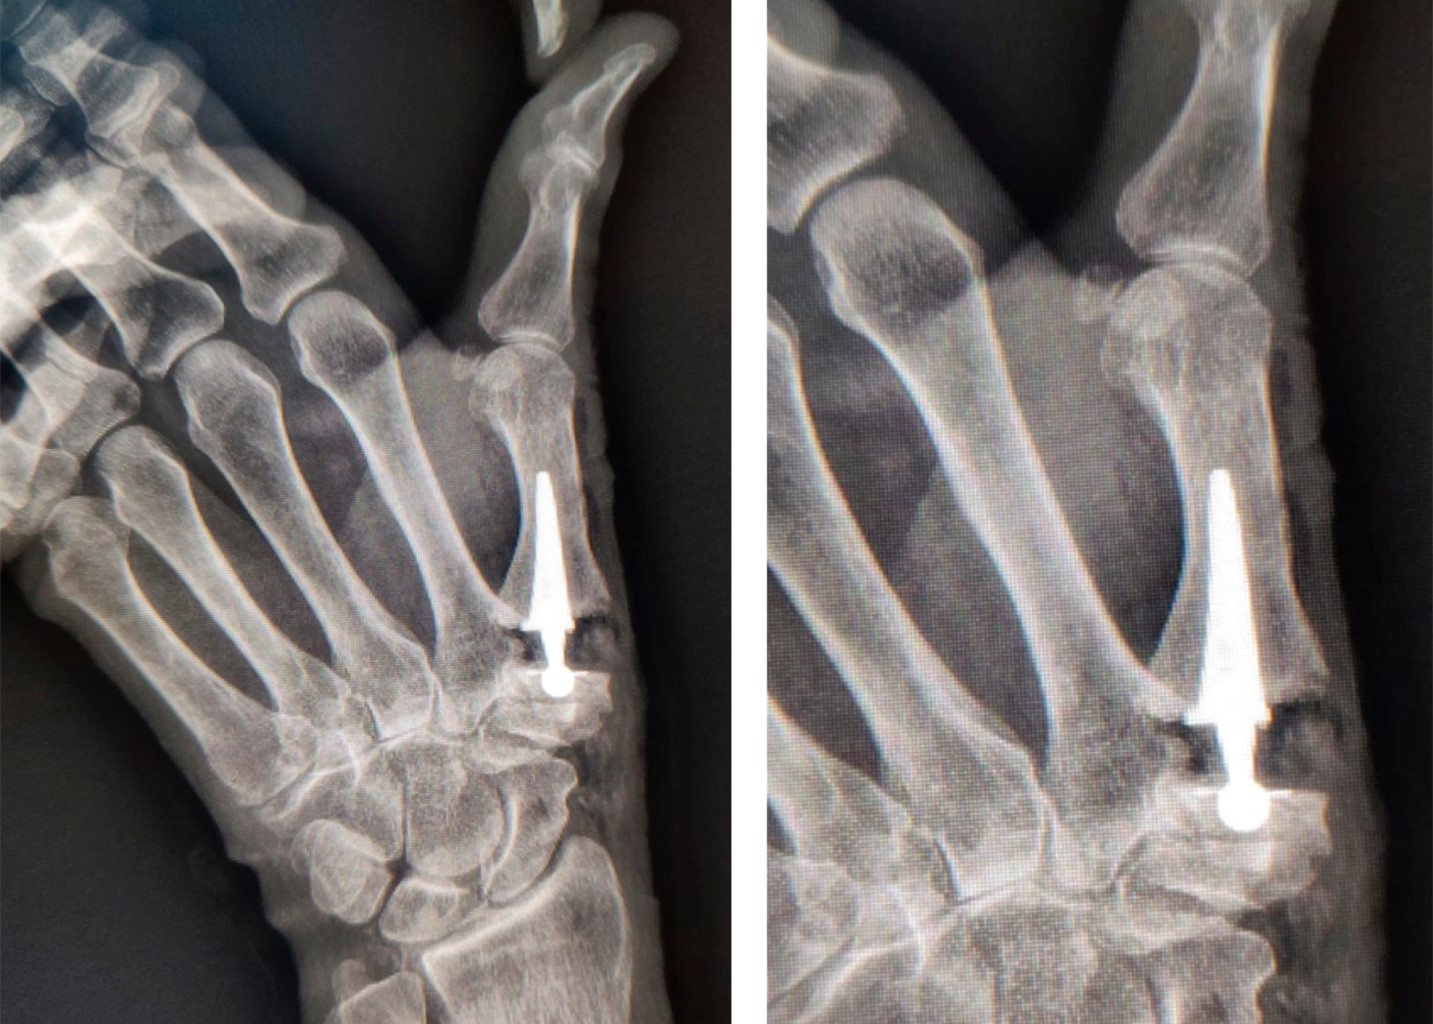

La artrosis trapecio-metacarpiana o rizartrosis es una patología que produce dolor, disminución de la fuerza y pérdida de destreza en la movilidad del pulgar, limitando la función global de la mano. Afecta a 20% de la población mayor de 50 años, principalmente en la mujer; provoca desgaste crónico y progresivo del cartílago que, en la mayoría de los casos, ocurre en ambas manos. Son típicos los episodios de dolor intenso en la base del pulgar que aumentan al movimiento y al realizar esfuerzos con la mano. Los movimientos del pulgar se reducen, lo que ocasiona rigidez progresiva. En los casos avanzados, se aprecia deformación por inestabilidad, subluxación y formación de osteofitos (Figura 1). La radiografía simple permite corroborar el diagnóstico utilizando la clasificación por estadios de Eaton y Littler (Tabla 1). Cuando el tratamiento médico conservador resulta ineficaz, se recurre a la cirugía. La finalidad de la prótesis trapecio-metacarpiana es eliminar el dolor y restaurar la longitud del pulgar, la fuerza y funcionalidad (Figura 2). El procedimiento quirúrgico por lo general se realiza de forma ambulatoria, consiste en eliminar la porción del hueso que está desgastada y reemplazarla con la prótesis, la recuperación es rápida y en dos o tres semanas se inicia la rehabilitación.

Figura 1